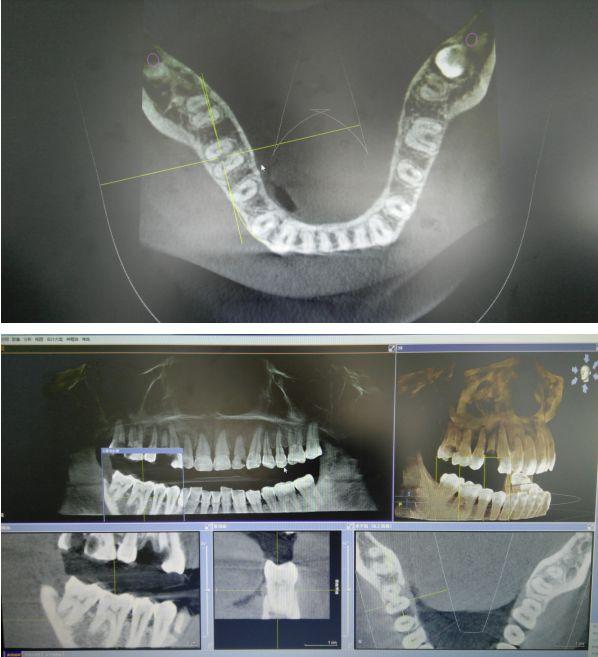

我院口腔科配備的西諾德口腔CBCT(錐形束CT),在業(yè)界被譽為神奇的“慧眼”,它能夠幫助口腔醫(yī)生詳細,清晰,了解患者口腔內(nèi)部的情況,是世界牙科聯(lián)盟指定的品牌儀器,具有當前世界先進的技術(shù)優(yōu)勢。

1.采集的信息量更多,采用錐形束360°容積掃描方式。

2.掃描范圍更大,掃描時間更短。

3.輻射劑量更低,一次CT拍攝只有29uSv,僅為普通CT的幾十分之一。

4.更高空間分辨率,對于頜面部骨骼和牙齒等硬組織的顯示比普通CT清晰約10倍。

5.影像后期處理功能強大,可以任意層厚、任意層距、任意切面,多方位、多角度的觀察病變。

6.適用范圍更廣、診斷更加,牙齒種植術(shù)前骨量及密度分析,埋伏牙的定位,牙齒矯正前的頭顱測量,復雜的根尖周病變的診斷,阻生齒拔除方案的詳細制定,頜骨囊腫范圍的確定,顳下頜關(guān)節(jié)骨質(zhì)的檢查等。

由于XG 3D/Ceph分辨率高,可以分辨人體組織內(nèi)細微的差別,使影像診斷的范圍大大擴大。尤為重要的是8*8cm視野的掃描一次即可對口腔上下頜全部的組織及上頜竇腔及下頜神經(jīng)管結(jié)構(gòu)進行重建,為出診患者的綜合觀察及常規(guī)攝影提供了支持。

CBCT掃描可準確分析頜骨植入?yún)^(qū)的骨質(zhì)、骨量、骨密度及植體與下頜神經(jīng)管、上頜竇的關(guān)系,臨床醫(yī)生可以在圖像上模擬種植,直接與患者進行溝通及交流,并可指導手術(shù)者在手術(shù)方案中避開危險區(qū)域,手術(shù)的性。此外,臨床醫(yī)生還可以利用CT數(shù)據(jù)進行數(shù)字模型重建,配合軟件預先做好手術(shù)模板使種植手術(shù)更快捷。